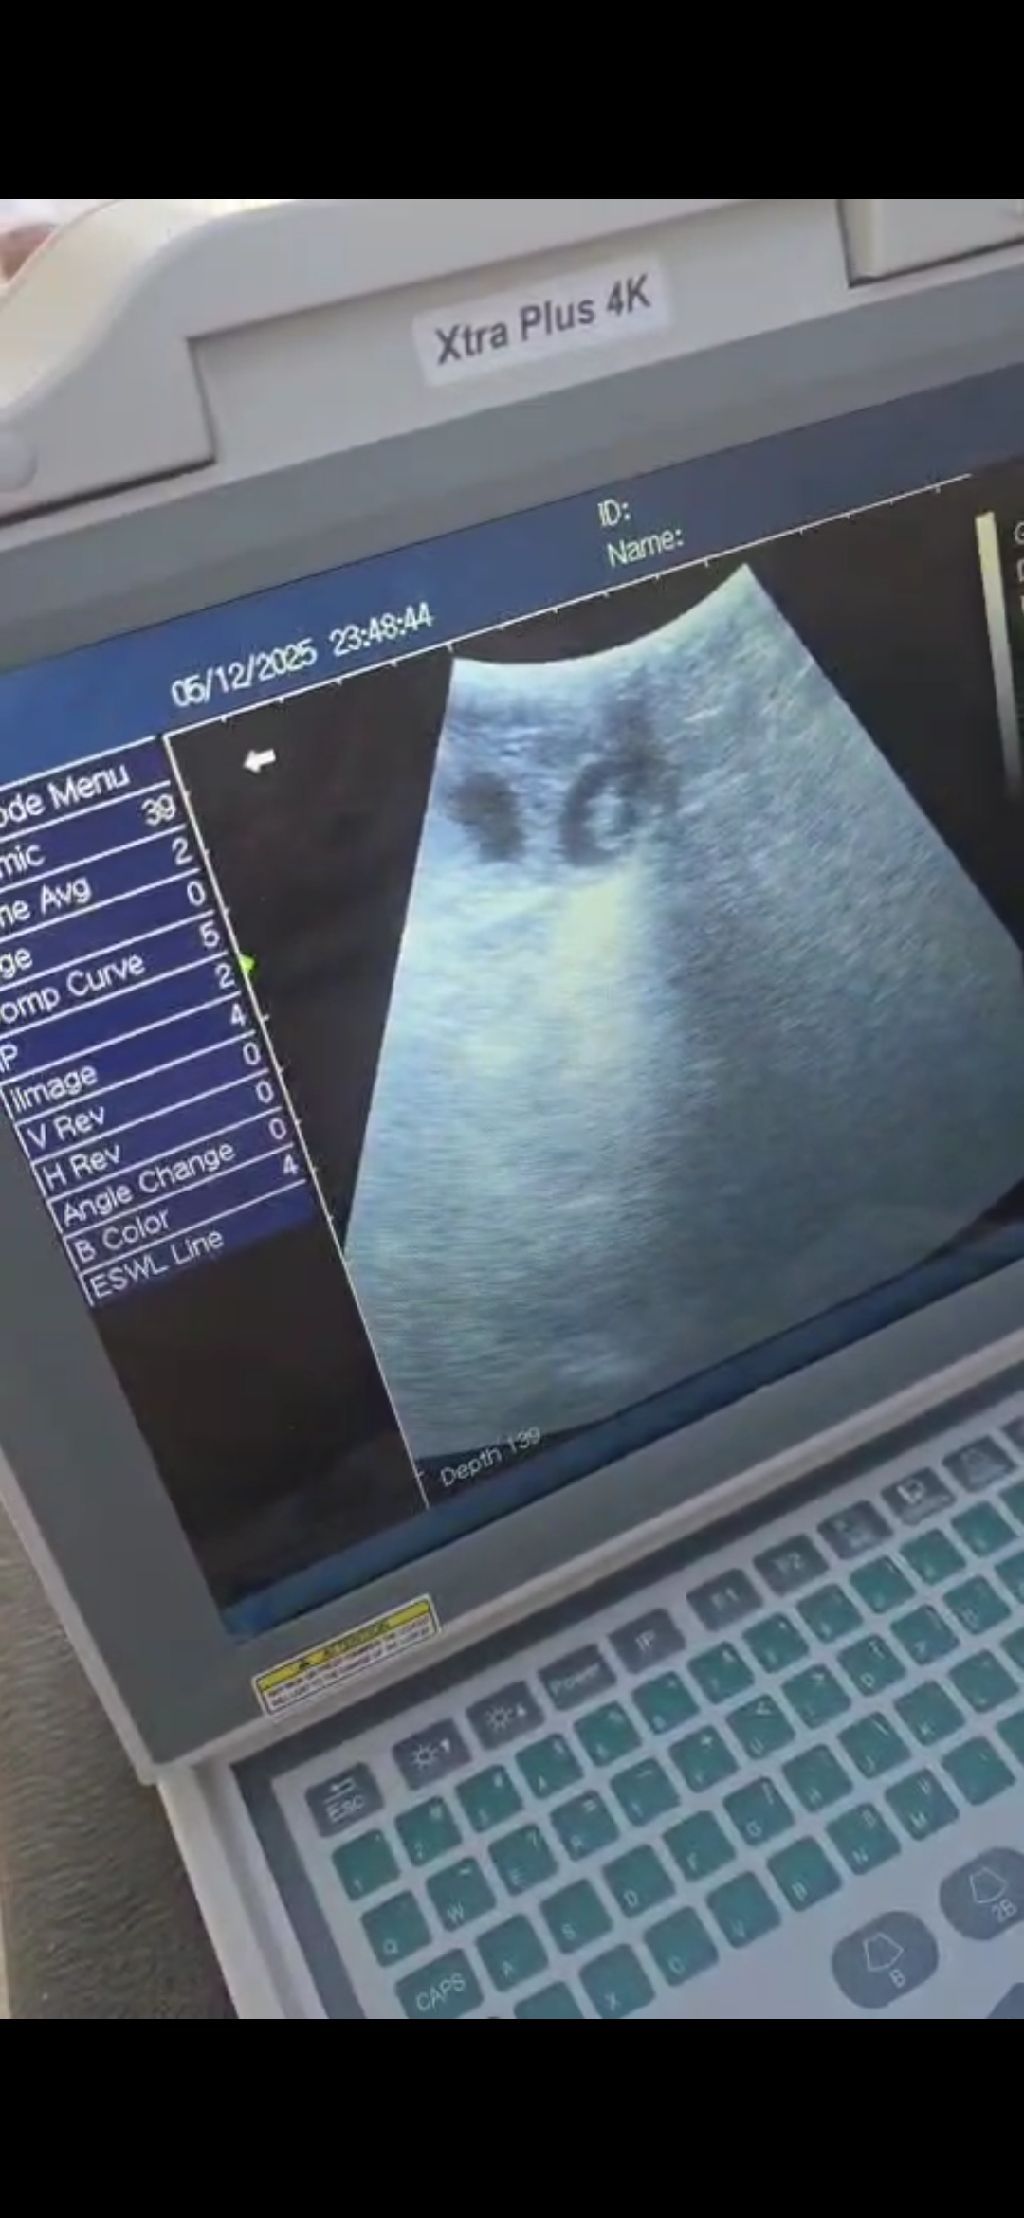

Medical Equipments For Sale in Medina Saudi Arabia

جهاز سونار لتشخيص الأغنام والابل من عمر 21 يوم بسعر مناسب أطلب مع د عبدالله فيصل

Medical Equipments For Sale in Medina Saudi Arabia

جهاز سونار لتشخيص الأغنام والابل من عمر 21 يوم بسعر مناسب أطلب مع د عبدالله فيصل